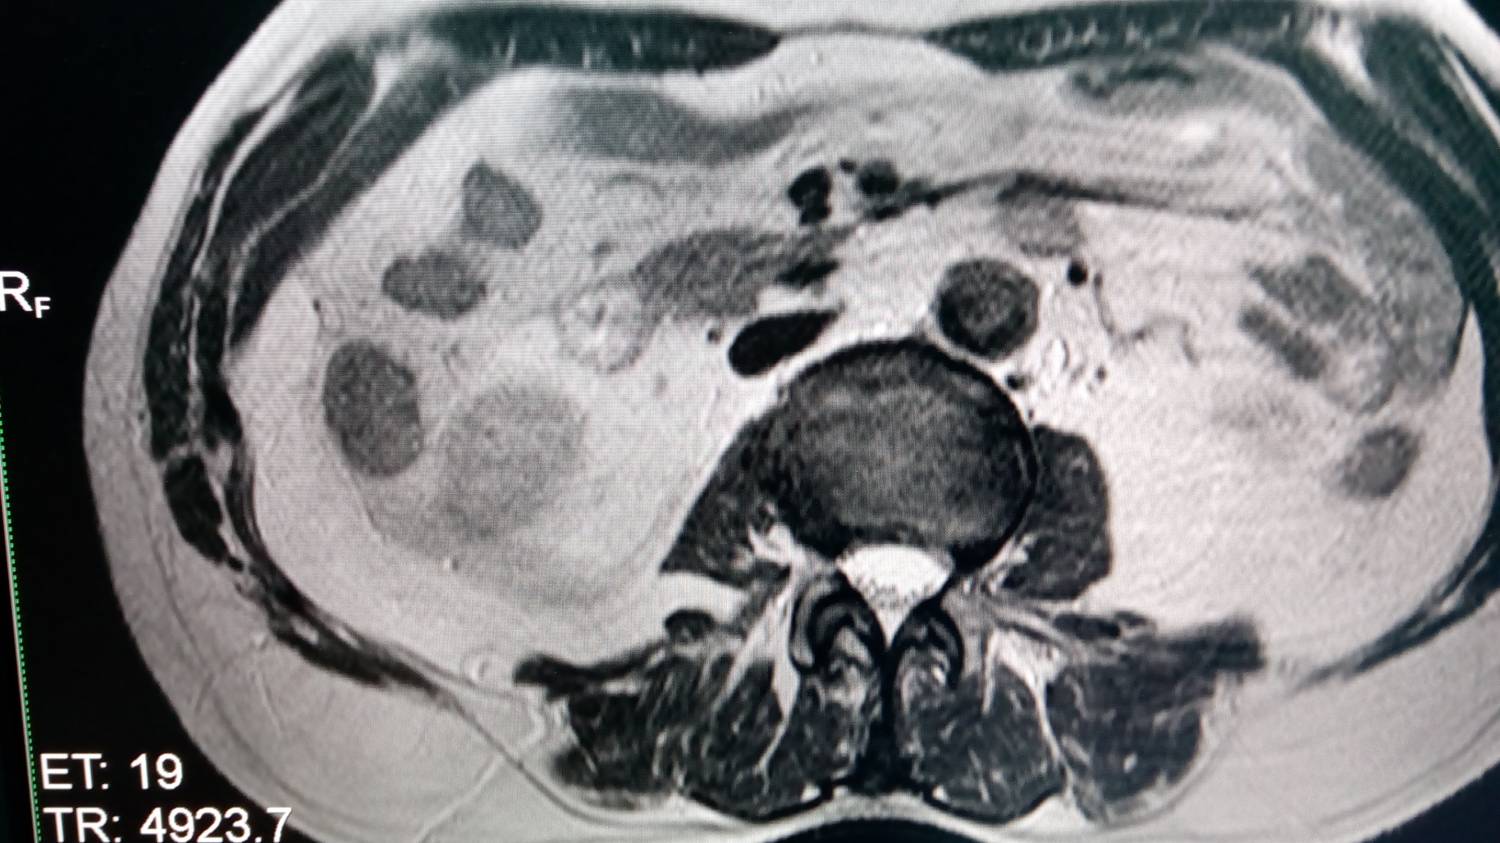

Периодически по непонятной причине на снимках появляются артефакты типа "ковер", снимки прилагаю,причем снимки находятся в одной серии - идет нормальный, следующий с ковром и потом опять нормальный, а также некорректно работает программа подавления жира.

7696509.jpg (135.8 Kb) · 7036744.jpg (154.2 Kb)